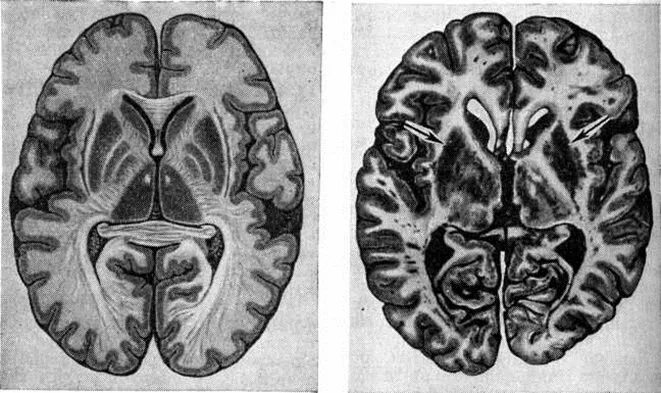

Диффузно атрофические изменения головного